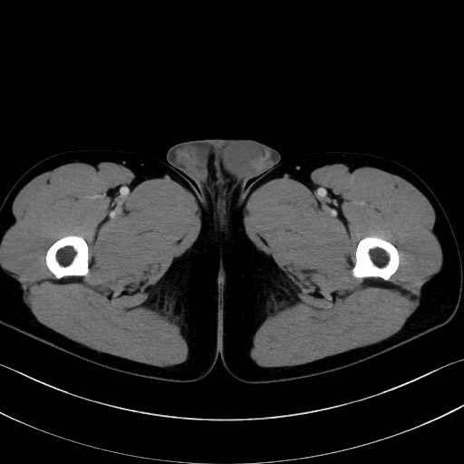

小殿筋(gluteus minimus)のCT画像の解剖

小殿筋 (Gluteus minimus)